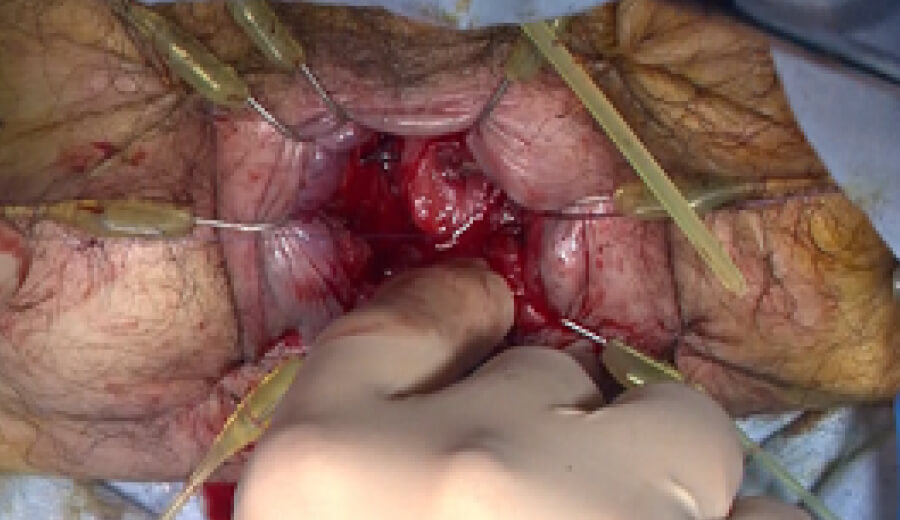

図3 潰瘍性大腸炎に対する大腸全摘術後の回腸嚢肛門吻合